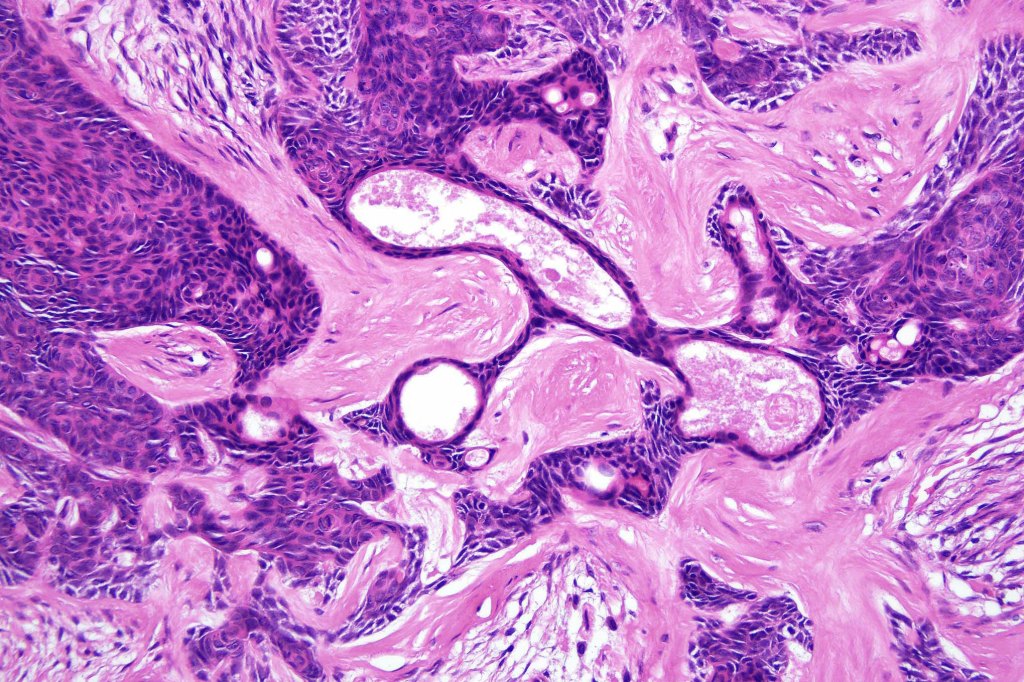

•Variable keratocysts

•A rich fibromyxoid mesenchymal stroma with variable papillary mesenchymal bodies (sometimes these are absent)

•Variable features include amyloid, focal granulomatous inflammation associated with free keratin & calcification